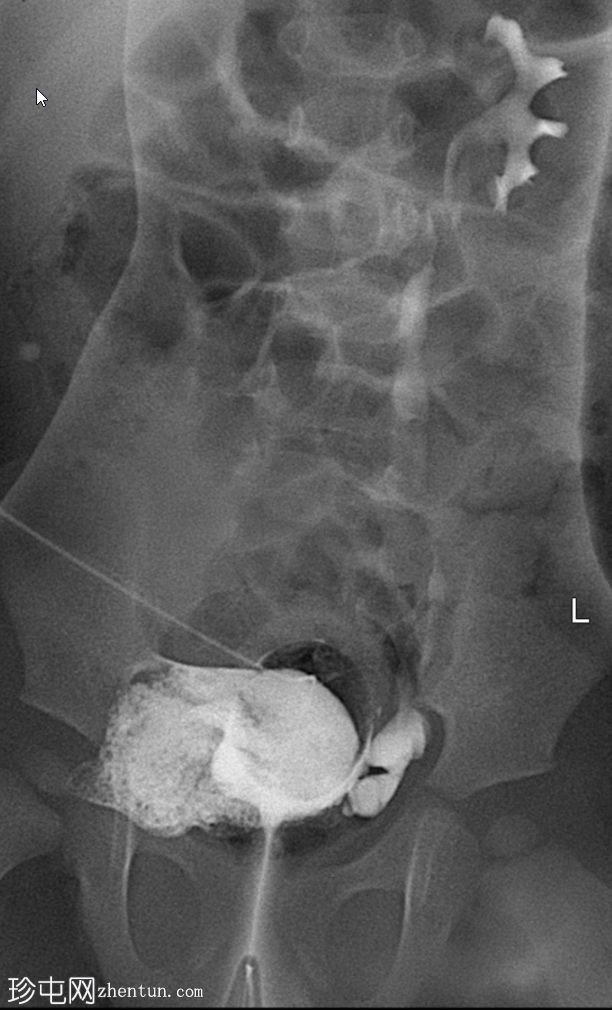

斜位片(纱布阻塞)

可见脐尿管开口通畅;在充盈期,造影剂经脐尿管自由流出,导致膀胱充盈不足。经脐尿管开口置入Foley导尿管并充盈球囊;然而,造影剂持续渗漏,膀胱充盈仍然不足。

使用纱布进行外部压迫成功阻塞了脐尿管开口,膀胱充盈良好。左侧输尿管和肾盂肾盏系统可见膀胱输尿管反流,符合II/III级VUR。输尿管轮廓正常,无憩室,无管壁增厚。尿道显影正常,未见后尿道瓣膜或狭窄。无肾积水。

首次尝试使用Foley球囊阻塞脐尿管开口效果不佳。纱布阻塞法可提供更完整的密封,使造影剂得以充分滞留并充盈膀胱。这使得排尿期能够显示II/III级膀胱输尿管反流。